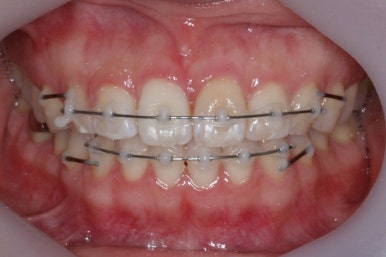

부산앞니교정 키다리아저씨치과에 처음 내원하셔쓸 당시의 입안 모습입니다.

앞니가 살짝 삐뚤어진 것을 볼 수 있고, 삐뚤어진 사이에서 약간의 틈새도 있었습니다.

예전에 치료 받으셨던 앞니 부분에 약간의 변색도 와서 미적으로 좋지 못한 상황이였습니다.